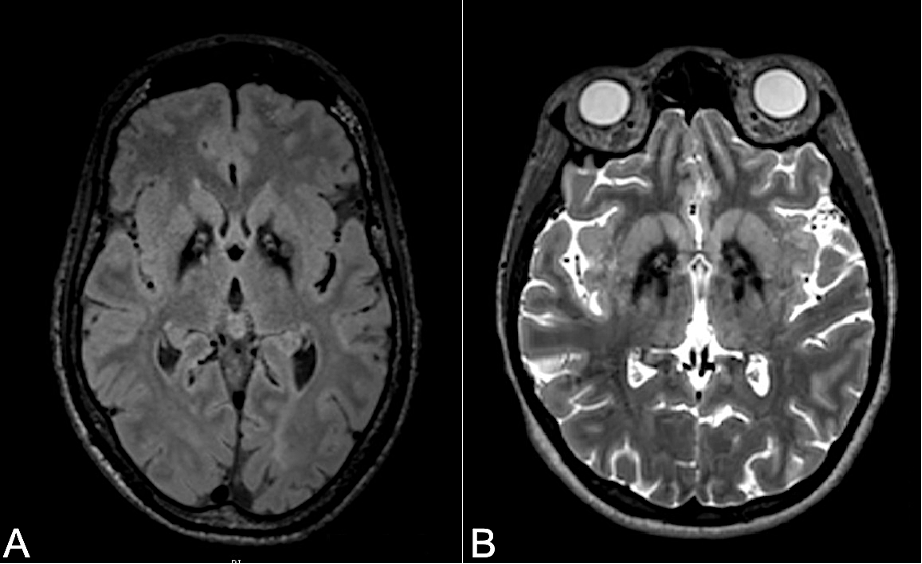

Results: Genetic study revealed 3 mutations (c.332T>A, c.1211A>T, and c.1405G>C) in heterozygosity and 1 mutation (c.377G>C) in homozygosity of the PANK2 gene. MRI showing “tiger eye” sign in the globus pallidus of both patients (Image 1 A and B). Treatment with botulinum toxin showed no improvement. Placement of DBS in July 2024 (♂STN and ♀GPi). Unified Dystonia Rating Scale (UDRS), post-botulinum toxin application, and post-DBS placement, with improvement of ♂ 11% and ♀ 63% (Graphic 1).

Image 1. RM (19.07.24) A ♂ 33 y. B♀28 y.